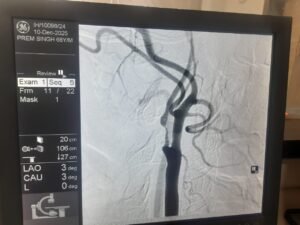

एक साल पहले प्रेम सिंह को स्ट्रोक हुआ था, जिससे उनके शरीर के बाएं हिस्से में कमजोरी आ गई थी। हालिया जांच में पता चला कि उनकी दाहिनी कैरोटिड आर्टरी में 95-99% तक गंभीर रुकावट थी, जो भविष्य में फिर से स्ट्रोक का बड़ा कारण बन सकती थी।

डॉक्टरों की मल्टीडिसिप्लिनरी टीम ने स्टेंट लगाने के बजाय सर्जरी को अधिक सुरक्षित विकल्प माना, क्योंकि रक्त नली में मौजूद प्लाक बहुत नरम और नाजुक था, जो टूटकर मस्तिष्क तक पहुंच सकता था। इसलिए Carotid Endarterectomy की सिफारिश की गई, जिसमें गर्दन की धमनी को खोलकर जमा प्लाक को सावधानी से निकाला जाता है।